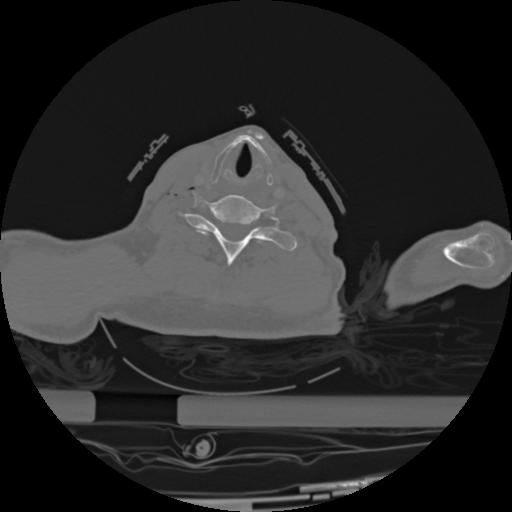

22 ANGIO,CE,Vol,0.5,ANGIO,,